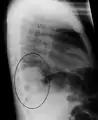

AP CXR showing left lower lobe pneumonia associated with a small left sided pleural effusion

AP CXR showing right lower lobe pneumonia

AP CXR showing pneumonia of the lingula of the left lung

Right upper lobe pneumonia as marked by the circle.

Left upper lobe pneumonia with a small pleural effusion.

Right lower lobe pneumonia as seen on a lateral CXR